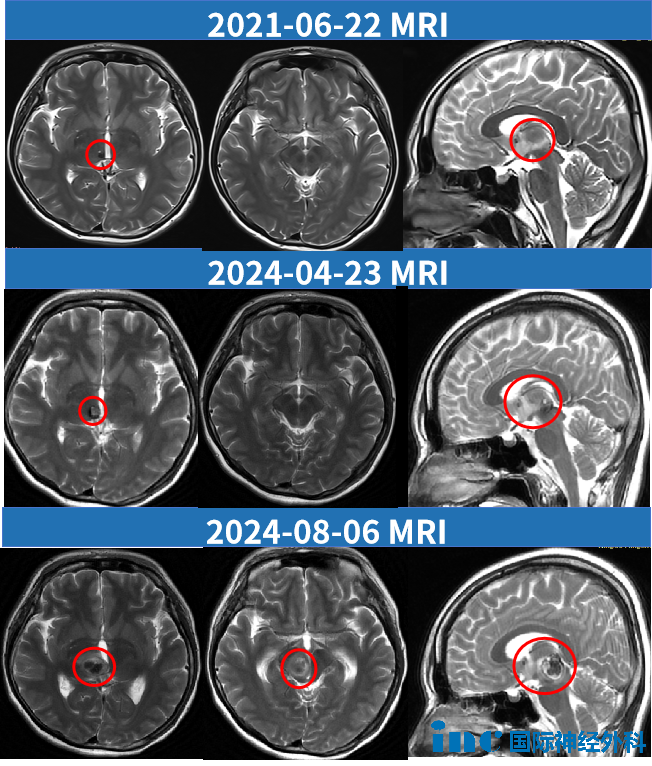

从最初的5至6毫米,到如今的22毫米,三年时间里,这颗"炸弹"已经长成了无法再被忽视的威胁。病灶变化脉络十分清晰:2021年6月,直径约5至6毫米,位于右侧丘脑,未累及中脑;2024年4月,约8毫米,略有增大,仍在丘脑范围内;2024年8月,22×19×13毫米,血肿从丘脑向下延伸至中脑,第三脑室已受压。